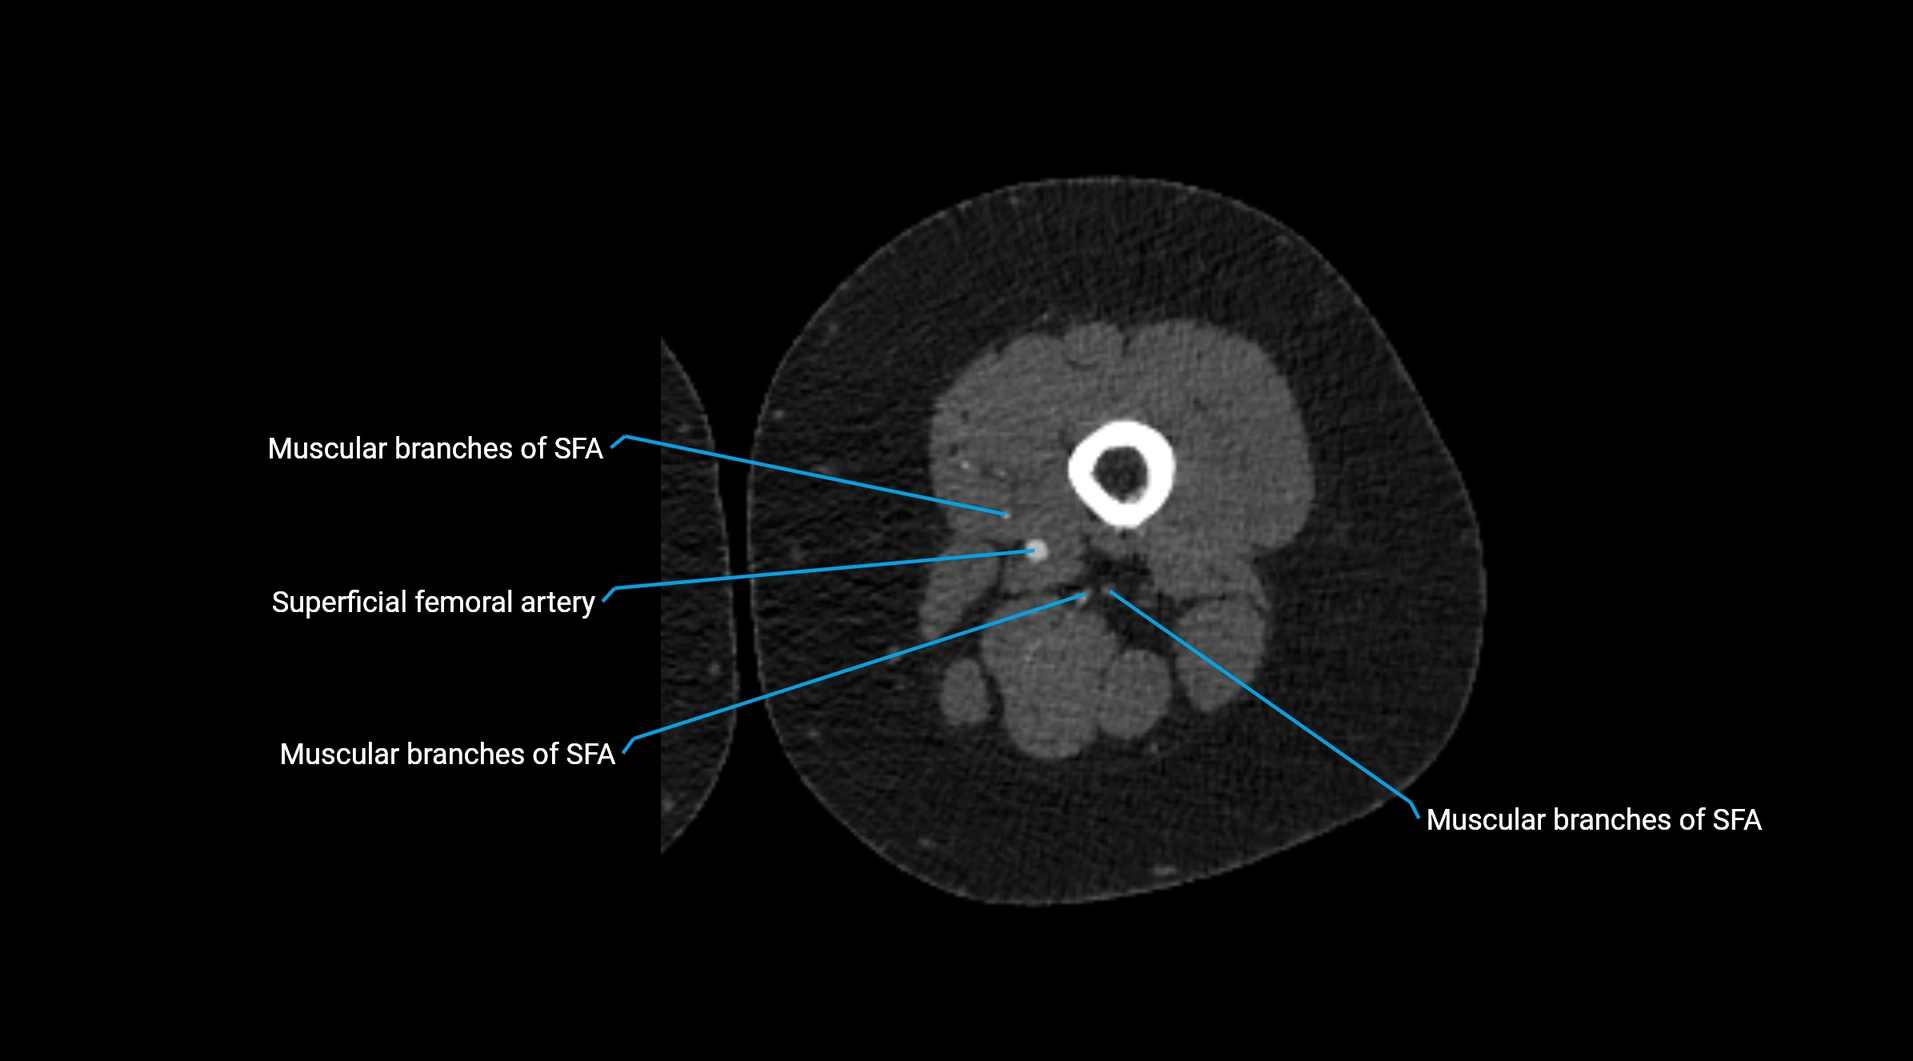

Contrast-enhanced CT (CTA):

• Gold standard for abdominal aortic imaging

• Provides excellent detail of lumen, wall, aneurysm, thrombus, and branch vessels

• Multiplanar and 3D reconstructions help in aneurysm measurement, stent graft planning, and dissection evaluation